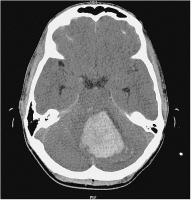

Abbildung 1: Kranielle Computertomographie (CCT): linkscerebelläre Blutung (Durchmesser 5 cm)

CCT